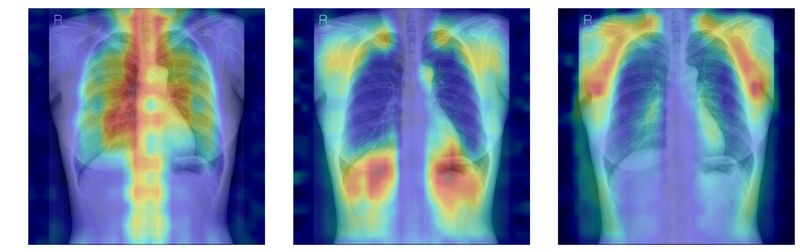

흉부X선에서 파운데이션 모델이 골다공증 판독을 위해 주목한 영역을 시각화한 이미지. 서울대병원 제공

‘차단 분석’은 모든 뼈 구조를 가린 뒤 특정 뼈를 순차적으로 노출했을 때 성능이 얼마나 향상하는지를 분석한다. ‘유의성 지도 분석’은 Grad-CAM으로 도출한 AI의 주목 영역이 실제 뼈 위치와 얼마나 일치하는지를 평가한다.

이를 통해 AI가 임상적으로 중요한 척추·늑골을 중심으로 예측 근거를 삼고 있음을 확인했다. 단순히 ‘정확도가 높은 모델’이 아니라 판단 근거가 의학적으로 타당한 모델임을 입증한 것이다.